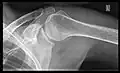

- Y-projection

The lateral contour of the shoulder should be positioned in front of the film in a way that the longitudinal axis of the scapula continues parallel to the path of the rays. This method reveals:[26]

- The horizontal centralization of the humerus head and socket

- The osseous margins of the coraco-acromial arch and hence the supraspinatus outlet canal

- The shape of the acromion

This projection has a low tolerance for errors and, accordingly, needs proper execution.[26] The Y-projection can be traced back to Wijnblath’s 1933 published cavitas-en-face projection.[27]

-

CR. shoulay film. -

Transaxillary conventional radiography -

Y-projection conventional radiography